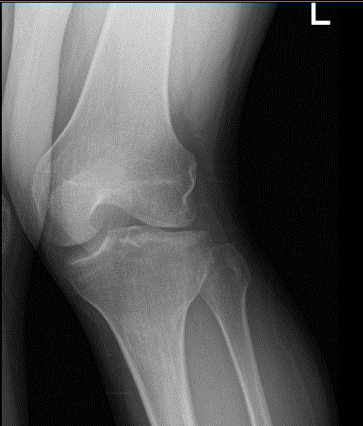

The patient presented X-ray results which showed that there is mild lateral compartment joint space narrowing. Otherwise unremarkable. Positioning is suboptimal as the patient is unable to straighten his knee.

Left knee X-ray AP and Lateral with Oblique 3 views